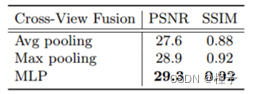

消融研究。表3和表4显示了交叉视图融合策略的消融分析和训练点的数量N。实验证明1.)MLP执行得最好,但是最大池化也是有效的,并且当视角在训练/测试数据中不一致时将是通用的解决方案,如第2.2节中所讨论的;(2)少点(例如,5,000)可能使训练期间的损失和梯度不稳定,导致性能下降; 10,000个点足以实现最佳性能,并且使用10,000个点进行训练比使用整个CT体积进行训练的基于体素的方法稀疏得多(即,2563或1283)。我们尝试使用不同的编码器,如预训练的ResNet 18 [8],其模型参数比U-Net [18]更多。然而,ResNet 18没有带来任何改善(PSNR/SSIM:29.2/0.92),这意味着U-Net足够强大,可以在此任务中进行特征提取。